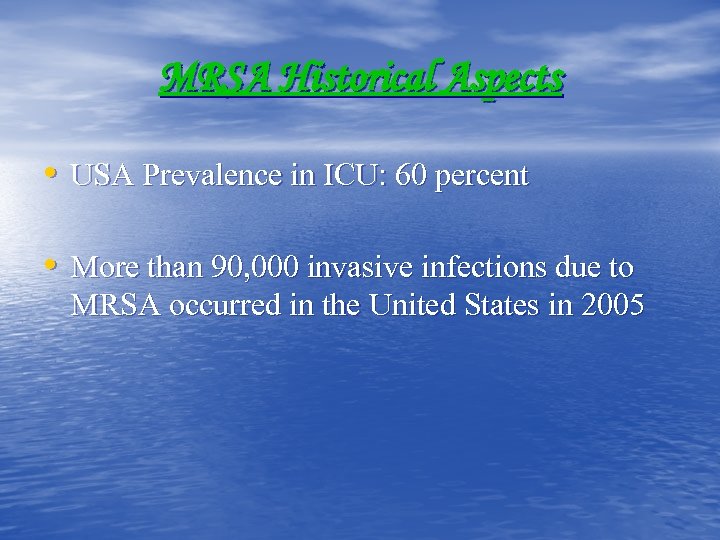

MRSA Historical Aspects • USA Prevalence in ICU: 60 percent • More than 90, 000 invasive infections due to MRSA occurred in the United States in 2005

MRSA Historical Aspects • USA Prevalence in ICU: 60 percent • More than 90, 000 invasive infections due to MRSA occurred in the United States in 2005